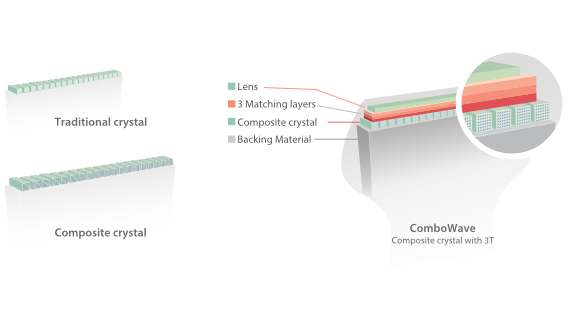

Transdutores